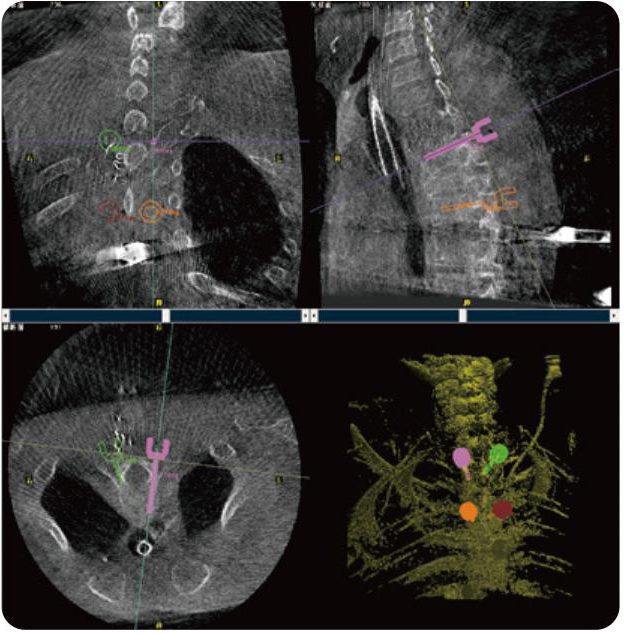

PL300B可應(yīng)用于多節(jié)段脊柱外科手術(shù),輔助醫(yī)生定位病灶部位,為脊柱外科手術(shù)(經(jīng)皮椎體成形術(shù)、椎弓根螺釘內(nèi)固定術(shù)等術(shù)式)提供術(shù)前手術(shù)流程規(guī)劃、入釘位置、角度可視化引導(dǎo),模擬仿真入釘輔助。

PL300B搭配普愛(ài)醫(yī)療自主研發(fā)生產(chǎn)的平板3D C形臂,借助一體化自適應(yīng)配準(zhǔn)( 軌跡配準(zhǔn))技術(shù),通過(guò)追蹤C(jī)形臂三維采集軌跡,自動(dòng)完成圖像坐標(biāo)建立和系統(tǒng)坐標(biāo)配準(zhǔn)。配準(zhǔn)精度更高,操作步驟少,系統(tǒng)運(yùn)作效率高。